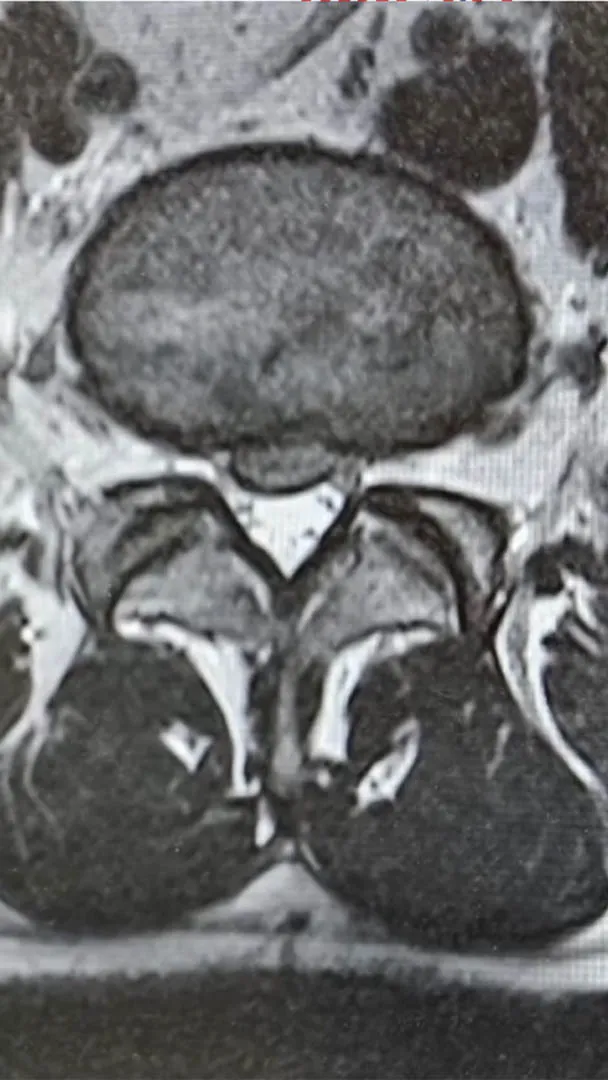

Turek se vyjádřil i ke svému zdravotnímu stavu. Upřesnil, že má „poměrně drsně“ vyhřezlou ploténku. V neděli byl podle svých slov na magnetické rezonanci. Vysvětlil, že před několika dny prakticky přestal chodit. Dostával infuze a silné léky na bolest. S ploténkou měl potíže už v minulosti.